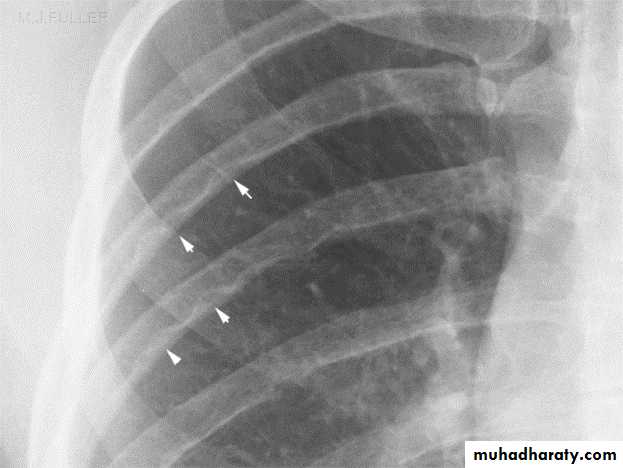

In infantile type ECG and CXR show right ventricular hypertrophy with cardiomegaly and pulmonary edema while in older children they show left ventricular hypertrophy and a mildly enlarged heartIn older children(>8 years) the chest x-ray film may show notching

of the ribs due to the development of collaterals.